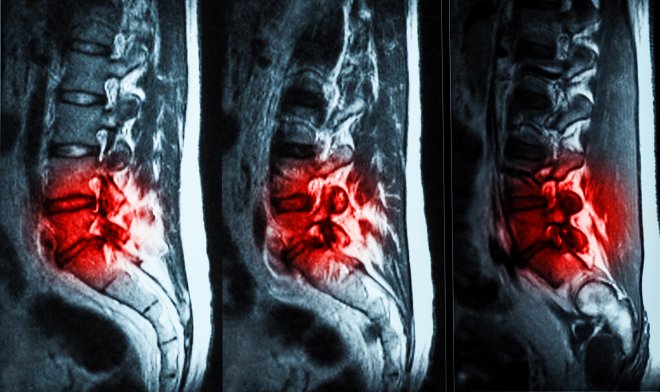

Хроническими болями в пояснице по причине изношенности межпозвоночных дисков страдают миллионы людей. Основная функция дисков — амортизация позвонков. Однако со временем диски изнашиваются, находящаяся внутри них жидкость вытекает, из-за чего их амортизационная функция снижается, что вызывает боли в позвоночнике и даже приводит к инвалидности.

Специалисты компании ReGelTec разработали гидрогель Hydrafil, который при введении в позвоночник заполняет трещины и травмы поврежденных дисков, частично восстанавливая утраченную амортизацию и снимая боль. В настоящее время препарат проходит испытания с участием 20 добровольцев, страдающих от хронических болей в пояснице, в возрасте от 22 до 69 лет.

Перед применением гель нагревают, превращая в густую жидкость, которая затем вводится шприцем в пораженные диски. Там, охладившись до температуры тела, она формирует имплант, по своим характеристикам почти ничем не уступающий межпозвоночному диску. Для оценки результата восстановления требуется еще полгода наблюдения у врача.

Уже есть первые обнадеживающие результаты. Используя 10-бальную шкалу, испытуемые отметили снижение болевых ощущений с 7,1 до 2,0, а боль, препятствующая заниматься повседневной деятельностью, «упала» с 48 до 6.